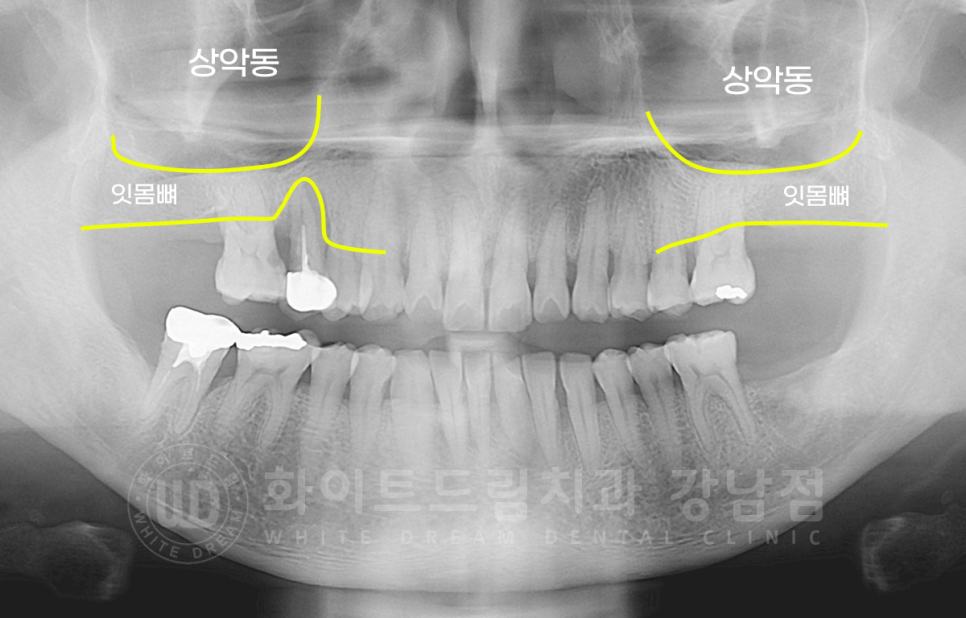

환자분의 초진 x-ray입니다.

서초동 어금니 임플란트 치료 전 / x-ray

10번대 : 17번 치아 상실, 15번 치아 잇몸 염증, 16번 치아 인접면 충치

15번 치아는 염증으로 발치하지만, 16번은 왜 뽑았나요?

15번 치아는 크라운 치료를 받은 치아인데, 크라운 내부에 2차 충치가 발생했고

이로 인해 16번 치아에도 충치가 전염된 상태였습니다.

신경치료를 진행하고 사용하기에는 충치의 범위가 컸고, 염증으로 뿌리 한쪽이 이미 겉으로 드러나 있는 상태였기에

해당 치아도 발치를 진행했답니다.

20번대 : 37번 치아 상실로 27번 치아 정출

30번대 : 37번 치아 상실

의 문제가 있으셨고, 문제 치아들은 모두 발치 후 임플란트를 식립하기로 했습니다.